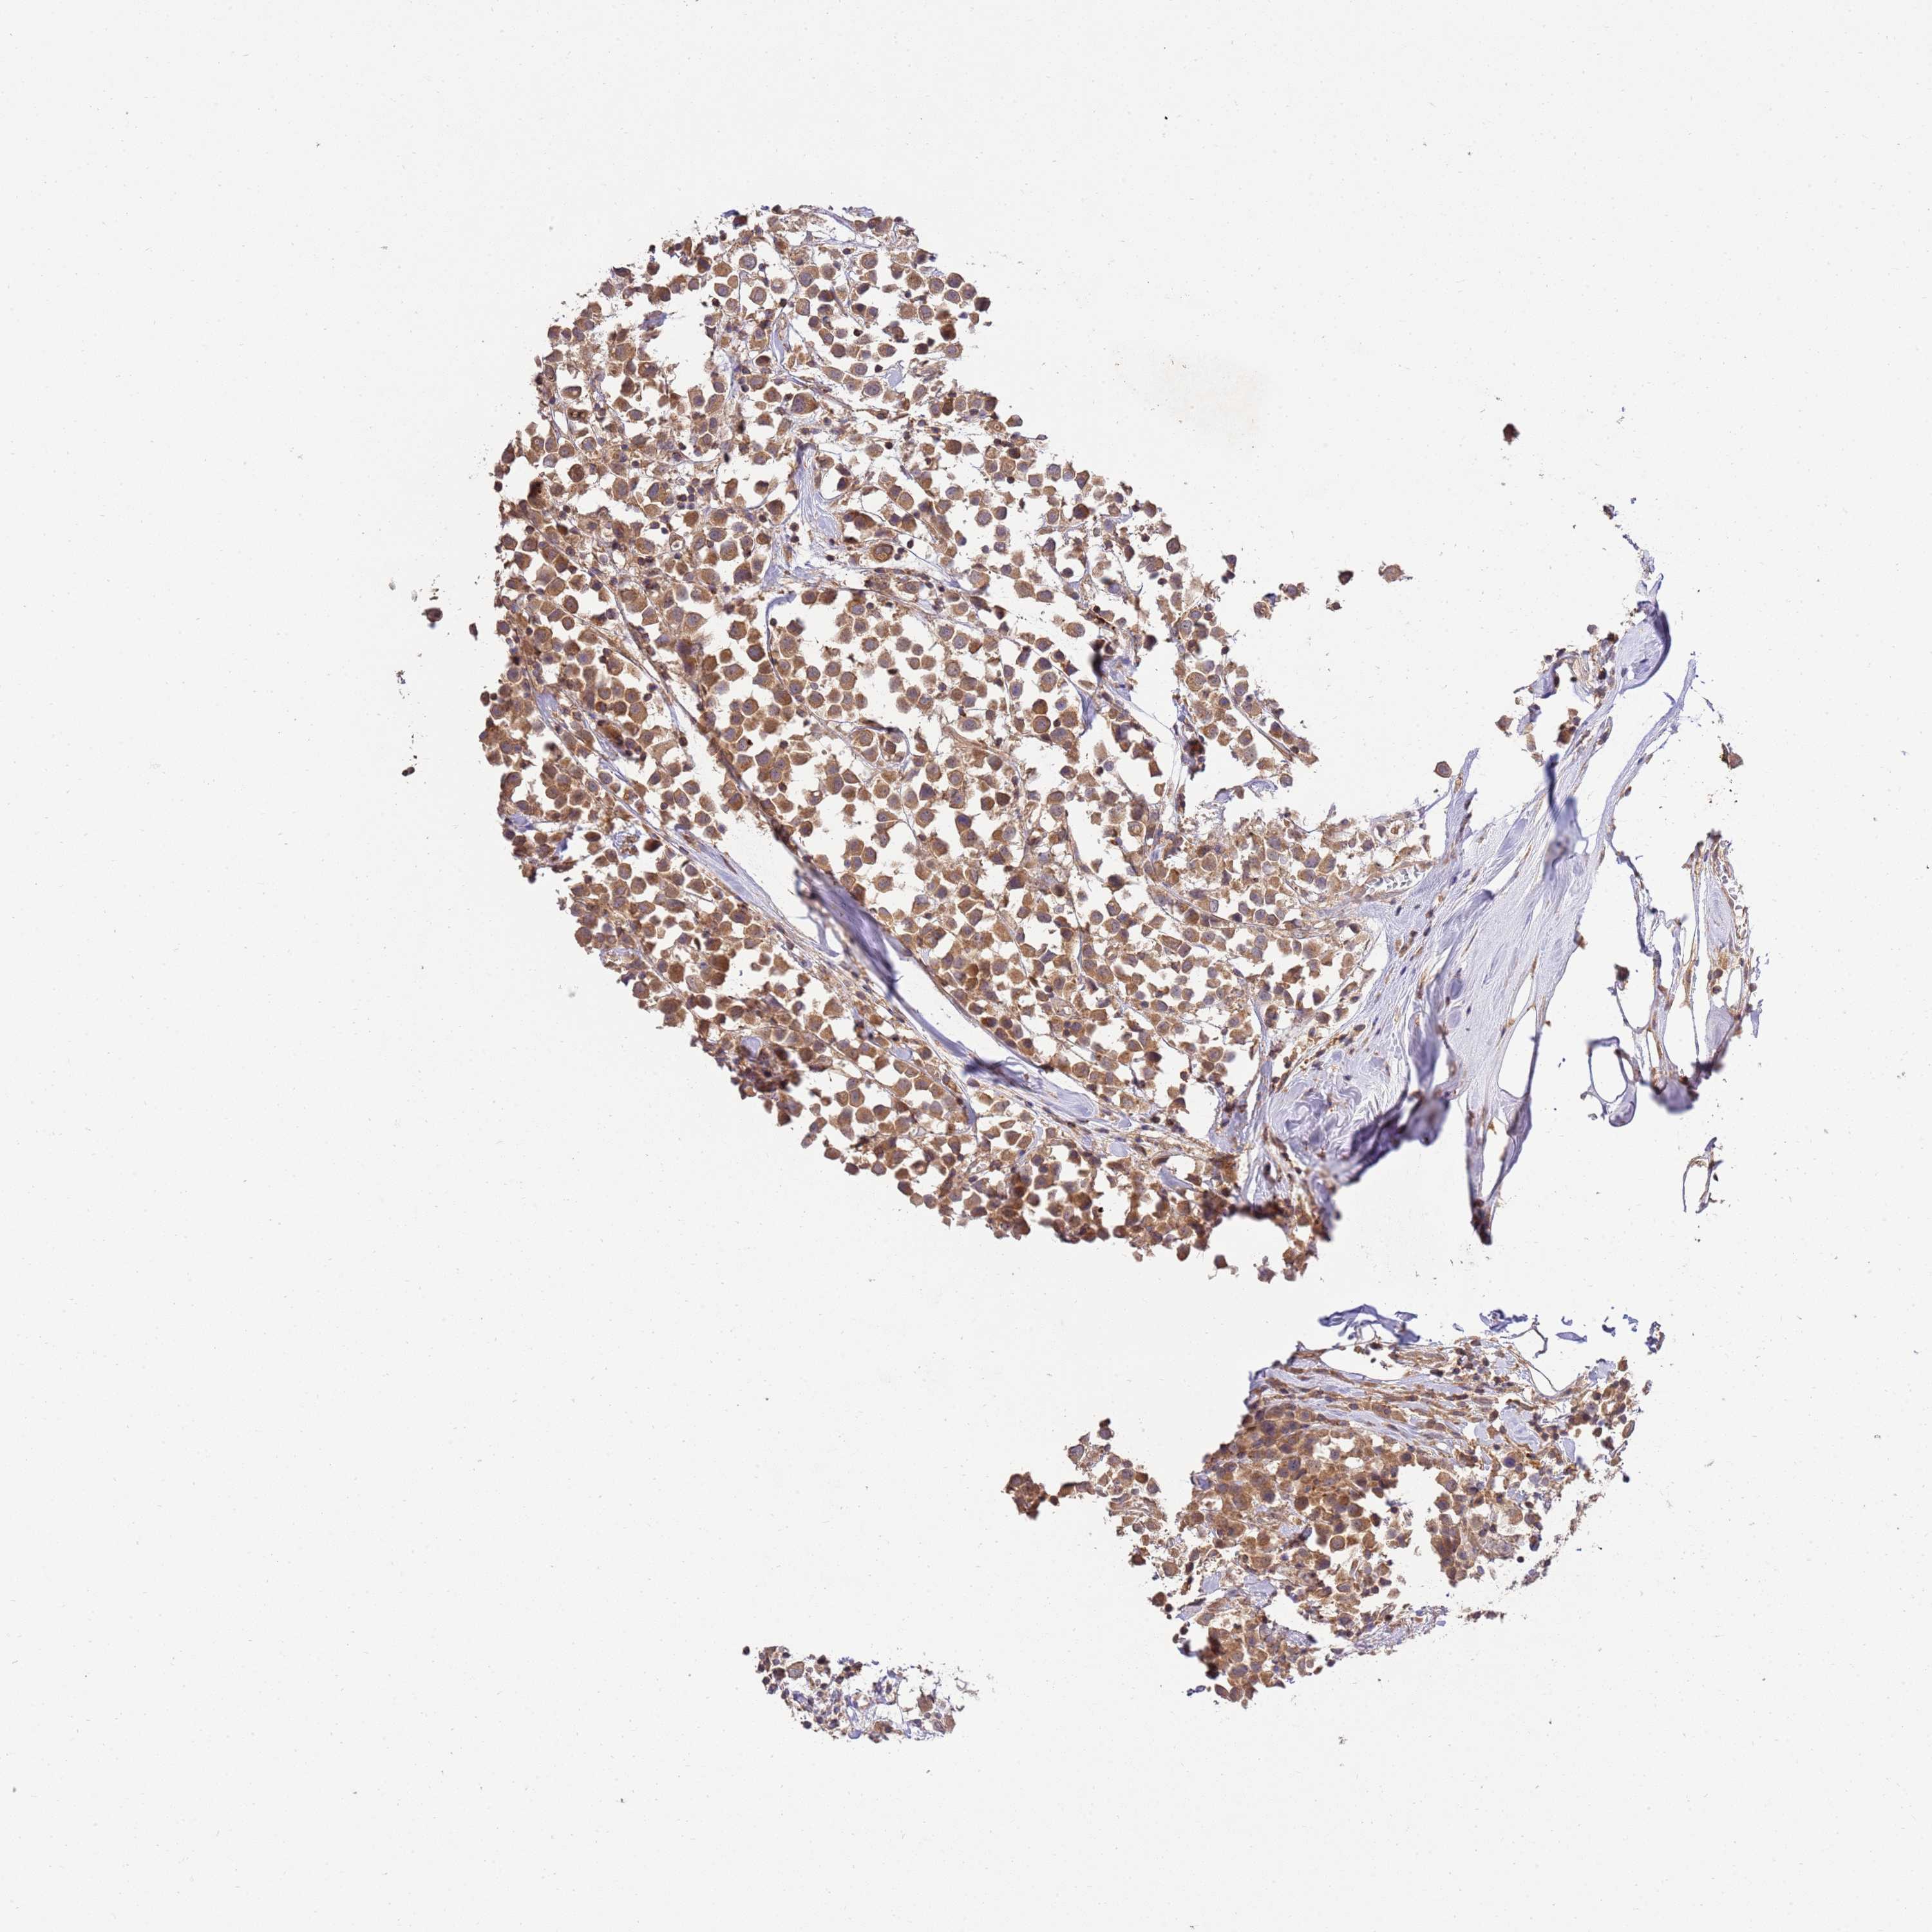

BRCA TCGA BRCA VALIDATION PROTEIN EXPRESSION

ANTIBODIES

AND

VALIDATION